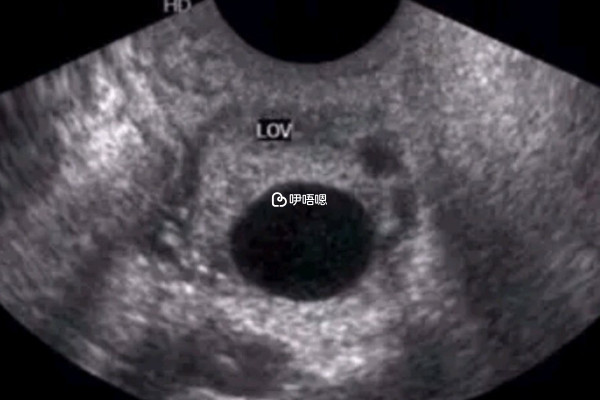

生男生女主要的影響因素還是男方的精子,當男性的y精子和卵子結合懷的就是男孩,和x精子相結合就會生女孩,從最開始精卵結合之後性別就已經決定了,所以任何公式都只是一個參考,而不是絕對的標準,以下是七七四十九公式算生男生女的方法: